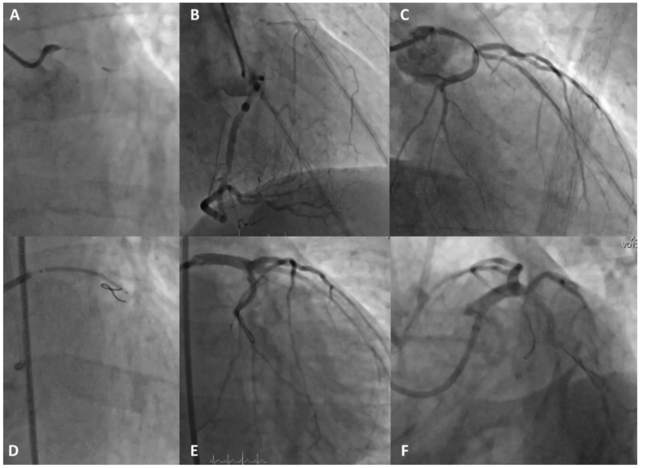

A 60-year-old male with chronic obstructive pulmonary disease and active smoking was admitted for positive treadmill test. He reported exertional chest pain 4 months ago; however, since then he had been symptom free. Echocardiography showed severe anteroseptal and mild inferoposterior hypokinesia, preserved wall thickness, and moderately reduced left ventricular ejection fraction. Coronary angiography revealed non-calcified chronic total occlusion (CTO) of the left main (LM) with microchannel toward the left circumflex (CX) artery (Figure 1A). Dominant right coronary artery (RCA), free of significant stenosis, supplied both left anterior descending (LAD) artery and CX with abundant transseptal and epicardial collaterals (Figure 1B). LAD and CX ostia were patent. Per the patient’s preference, we opted for percutaneous coronary intervention (PCI). The RCA was cannulated with Judkins 4.0, 6-Fr guiding catheter (left radial approach), LM with EBU 4.0, 7 Fr (right femoral approach; right radial approach failed). By using the antegrade-wire escalation technique, the LM was negotiated with a Fielder XTR (Asahi Intecc); however, only the CX could be accessed. After exchange for a Grand Slam wire (Asahi Intecc), balloon dilation with a non-compliant (NC) balloon up to 4.0 mm (Figure 1C) and wiring of the LAD with a Pilot 50 wire (Abbott) ensued. An Onyx 3.5- x 30-mm drug eluting stent (Medtronic) was implanted from the LM ostium toward the LAD (Figure 1D), followed by proximal optimization technique (POT)-kissing-POT sequence (NC 5.0 mm for POT). Technical and procedural success were obtained (Figures 1E, 1F and Video 1).

Oligosymptomatic or asymptomatic patients with unprotected LM-CTO are rarely encountered.1 We suggest that “functional protection” with potent collaterals, in addition to other favorable features, such as low/intermediate SYNTAX score (29), low Japan-CTO score (1), and absence of diabetes, should promote a PCI strategy. Long-term results of such PCIs are to be determined.